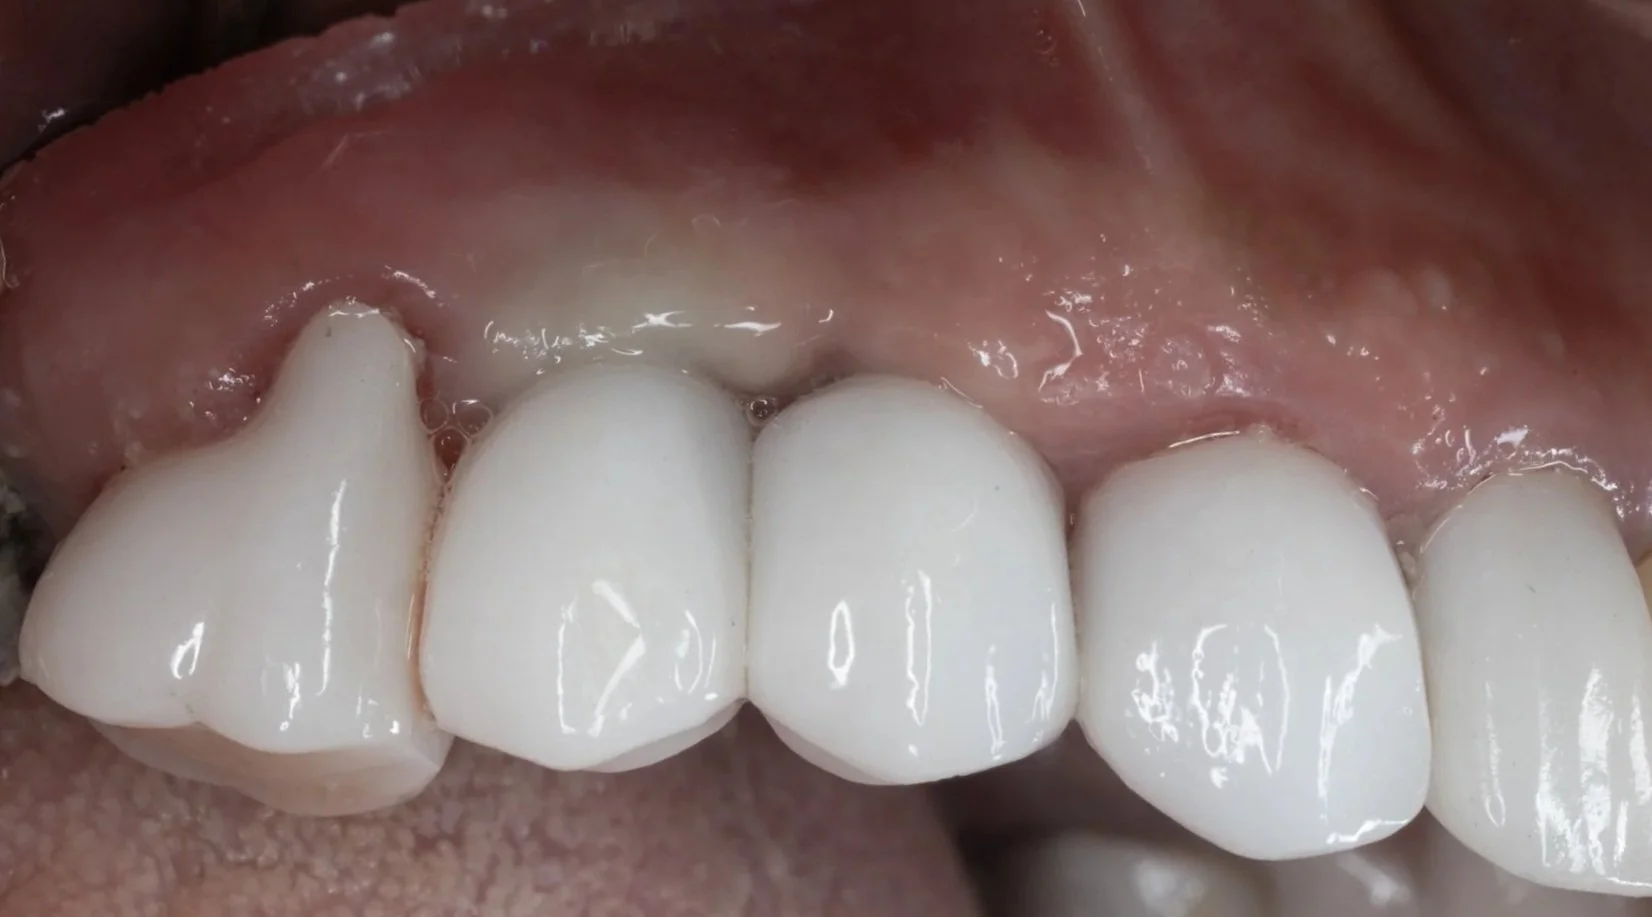

After three months of healing, digital impressions were taken using an intraoral scanner. The final crowns were delivered within one week, restoring both function and aesthetics. The patient was extremely satisfied with the result.

• Precisely placed implants following international protocols

• High-quality, natural-looking crowns with ideal gum relation

• Healthy gums with easy cleaning and no food accumulation

This case highlights how digital technology allows maximum precision, predictable outcomes, and long-term oral health.